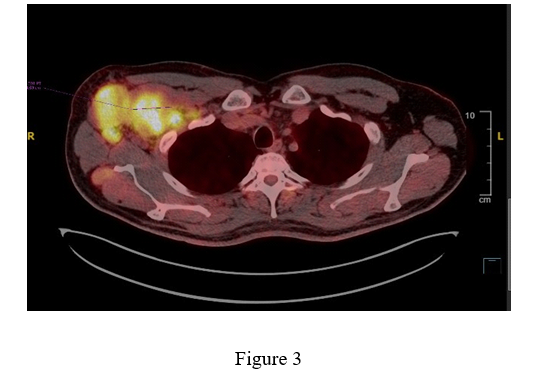

Ultrasound results found Right axillary large hypoechoic solid mass is seen measuring about 8.5x4cm; likely representing amalgamated lymph nodes. It shows increased vascularity inside with high resistivity index measuring 1, suggesting Highly suspicious large amalgamated lymph node mass; for true cut biopsy, see figure 1.

Figure.1: Patient was referred after that for medical oncology for further evaluation and additional investigation was undertaken.